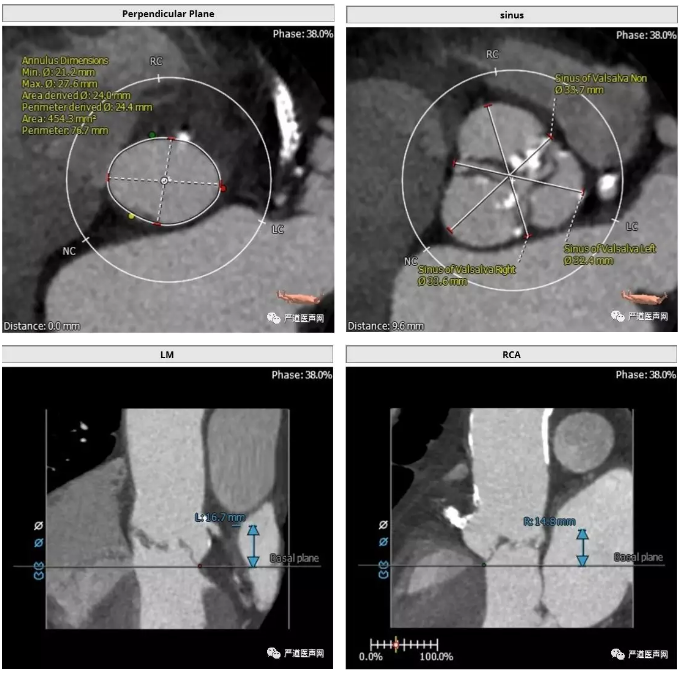

>>主动脉根部解剖: 三叶瓣,中度钙化,窦部结构尚可,冠状动脉高度尚可

1型二叶瓣,左右冠瓣融合,中度钙化,钙化集中在无冠窦侧,主动脉瓣瓣环